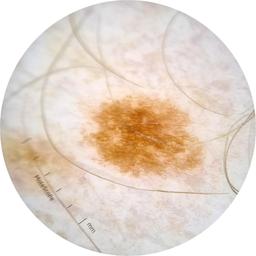

ISIC_6813604

MEL-SELF Trial, https://www.sydney.edu.au/medicine-health/our-research/research-centres/melself-project.html

acquisition_day 624

age_approx 75

anatom_site_1 Head and neck

anatom_site_general head/neck

diagnosis_1 Benign

diagnosis_confirm_type single image expert consensus

fitzpatrick_skin_type I

image_type dermoscopic

personal_hx_mm True

sex male